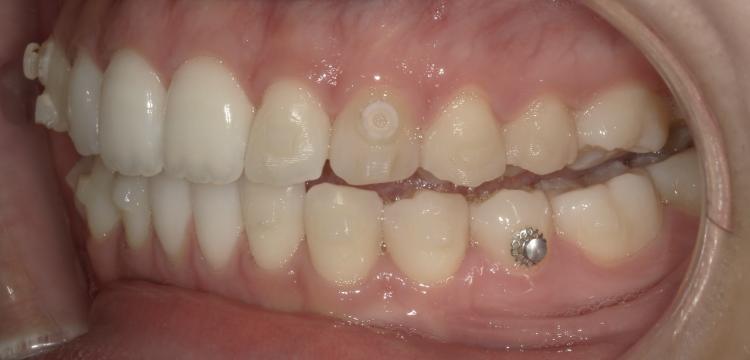

以下の写真はマウスピース矯正をはじめる前と現在の歯並びを比べたものです。

前歯の前突感がなくなりました!歯並びが変わるので噛み合わせにズレが出てくるのですが最後に噛めるように調整するので安心できます。